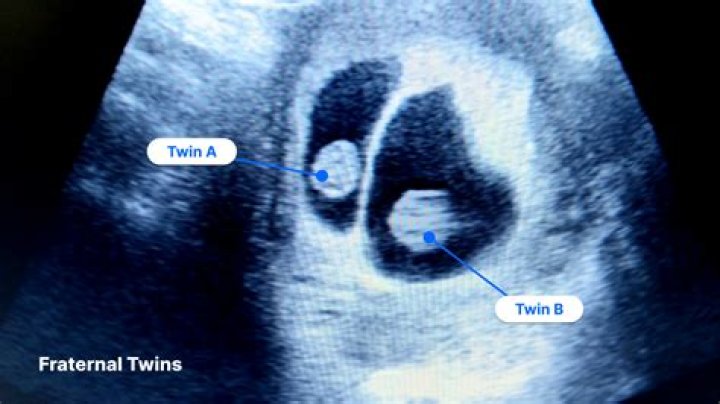

Diagnosis. Vanishing twin syndromeVanishing twin syndromeA vanishing twin, also known as twin resorption, is a fetus in a multigestation pregnancy that di...